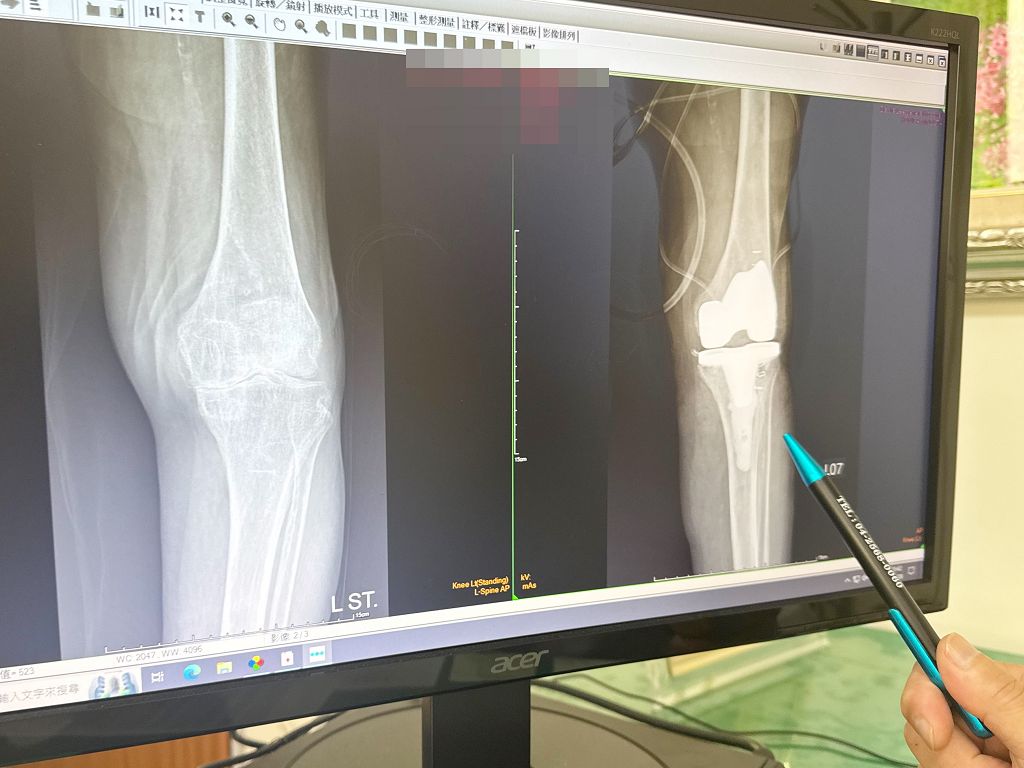

一名一百歲的劉姓人瑞阿嬤,長期務農再加上年紀大膝蓋退化導致罹患第四期關節炎,左膝蓋痛了兩個多月根本不能走,上廁所都很困難,嚴重影響生活,自己向兒子說要開刀治療。由於她罹患慢性阻塞性肺病,需要24小時用氧氣,因此,手術前跨科進行心肺功能評估,術中微創手術減少出血,術後也讓她吸足氧氣提高血氧容量後再復健,恢復情形良好。

大甲李綜合醫院副院長、骨科主治醫師王芳英表示,阿嬤在兒子的陪同下前來門診,經過檢查後,確認阿嬤罹患第四期退化性關節炎,建議要手術替換人工關節才能改善生活的不方便,隔了一個禮拜,阿嬤自己決定開刀,兒子也同意讓母親手術置換人工膝關節。

王芳英指出,阿嬤到門診就醫時便有帶氧氣,詢問有慢性阻塞性肺病,需要要24小時用氧氣,而且已經用了半年,為了完成阿嬤能生活自理的願望,術前跨科做心肺功能評估,會診胸腔科、心臟科、麻醉科,醫師評估能開刀,過程中阿嬤全程帶氧氣,儘量減少出血及軟組織的破壞,讓她能盡早復健。

王芳英說,阿嬤術後第二天便能下床復健,但是阿嬤血氧低,為了避免讓她昏倒,復健前先讓她吸足氧氣,提高血液中含氧量,再請她下床復健行走,儘量在10分鐘內完成復健。

王芳英強調,術後復健很重要,能幫助恢復關節活動度和肌力,減輕術後疼痛和水腫,預防沾黏,並維持身體平衡,讓人工關節發揮最佳功能,也能減少肺栓塞風險。